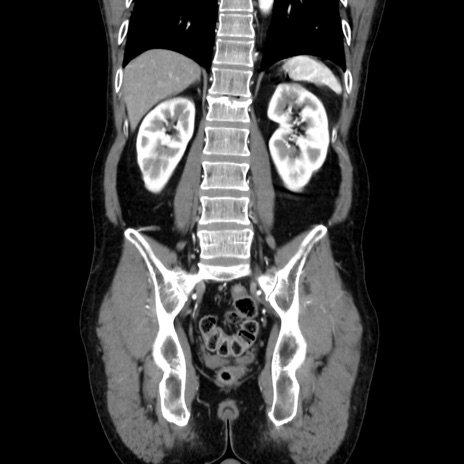

症例37(冠状断像)

【症例】40歳代 男性

【主訴】腹痛

【現病歴】4時間ほど前に電車に乗車中に臍部上より腹痛出現。徐々に増悪し起立困難となり、救急外来受診。生ものは数日食べていない。今朝お雑煮を食べた。

【身体所見】BT 36.8℃、BP 117/84mmHg、HR 91/min、SpO2 97%、苦悶様、腹部:臍上部広範囲圧痛あり、反跳痛±

【データ】WBC 8100、CRP 0.03